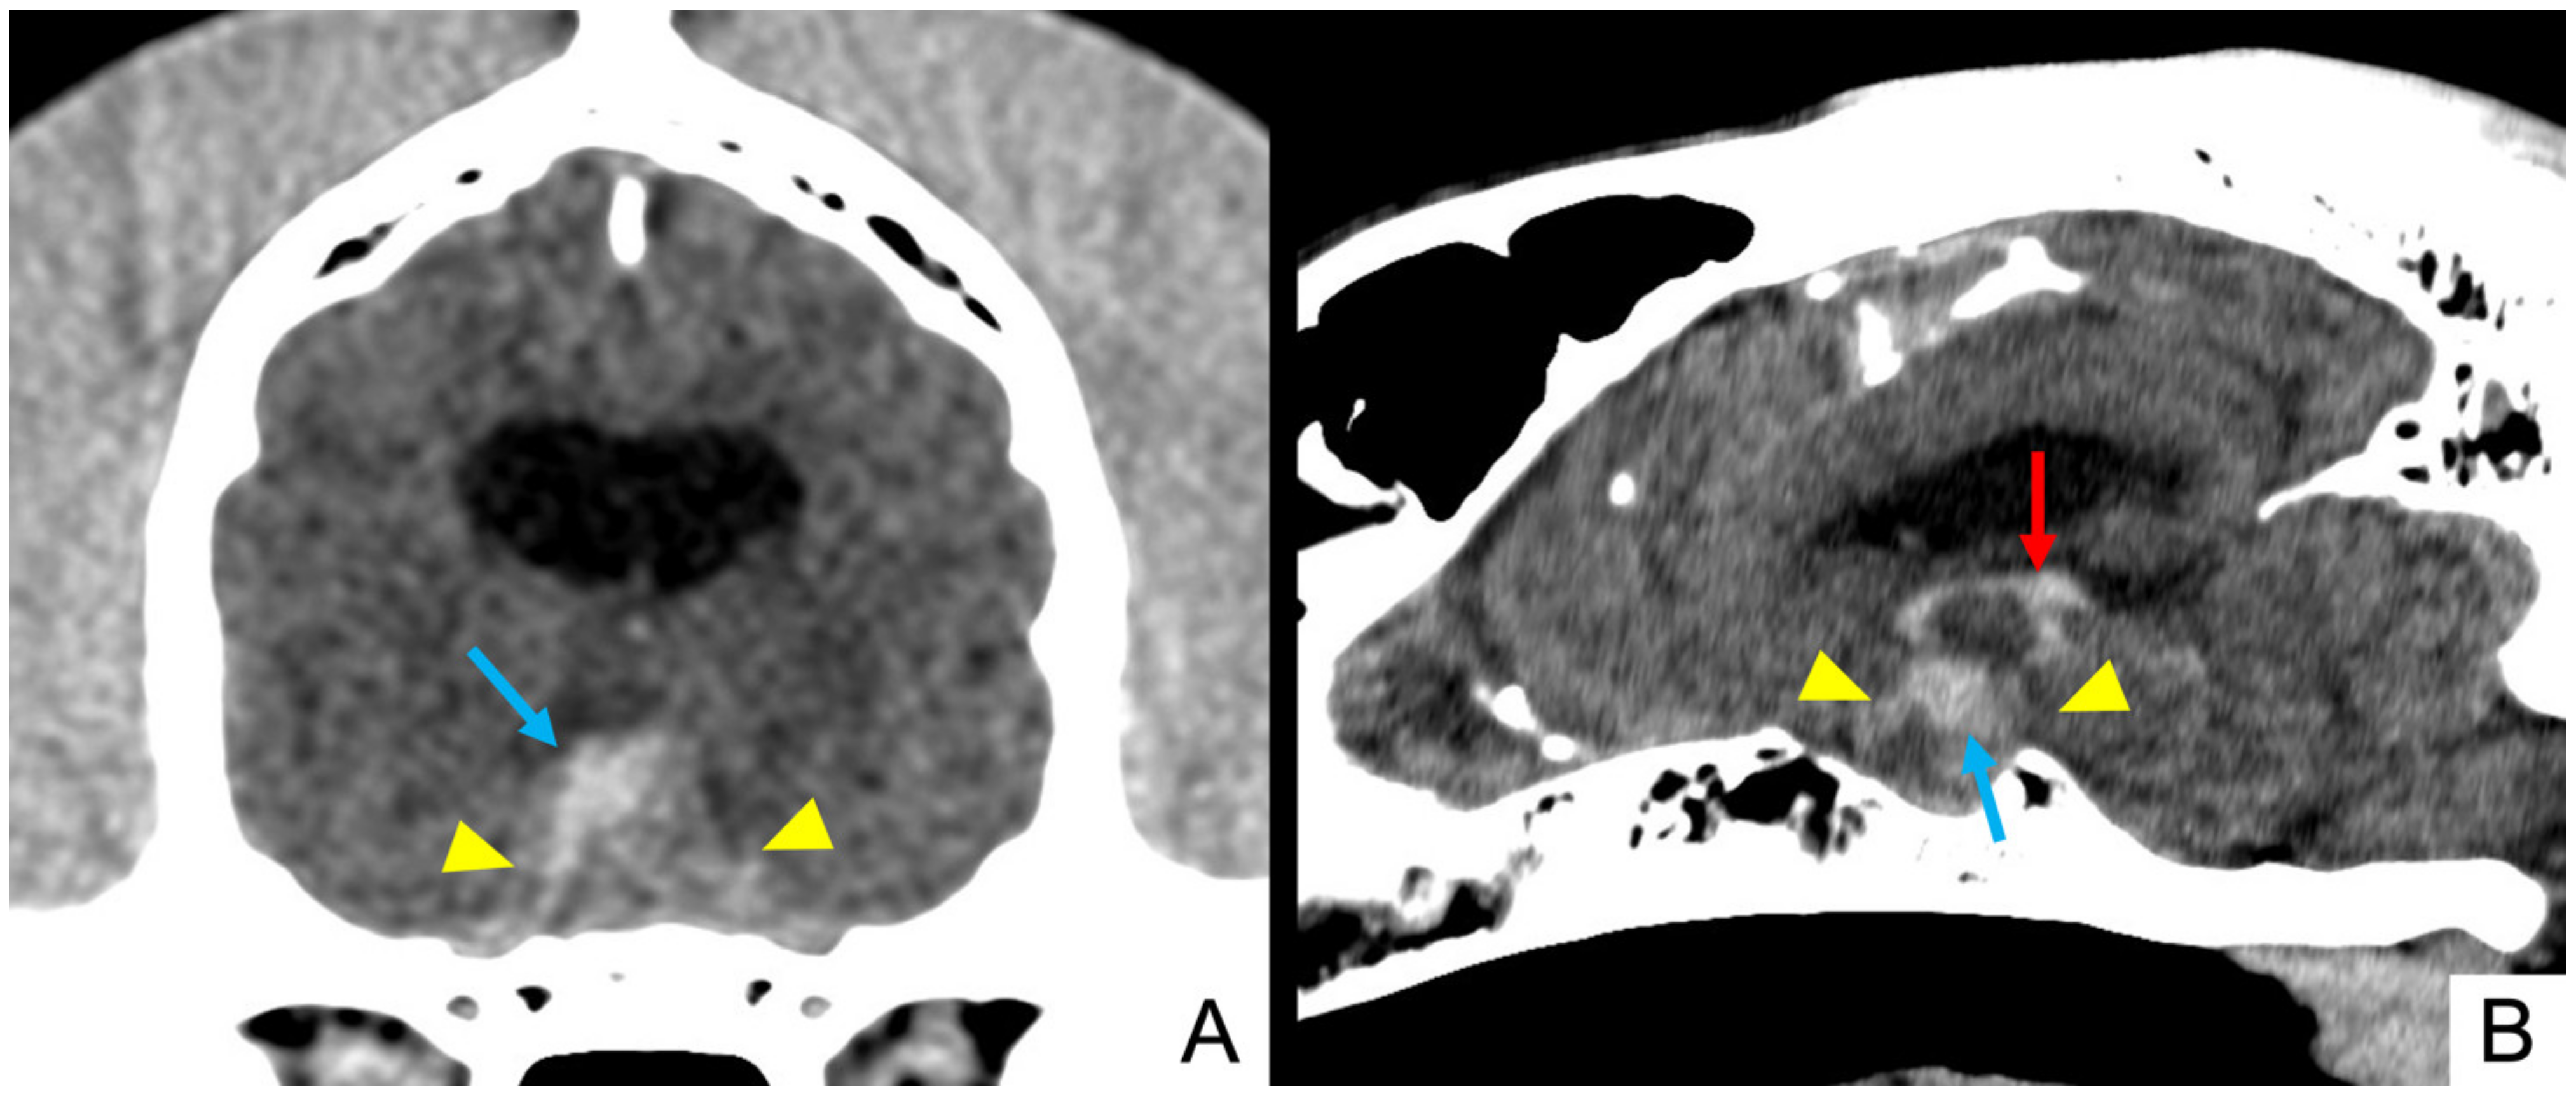

3.4. Imaging Findings